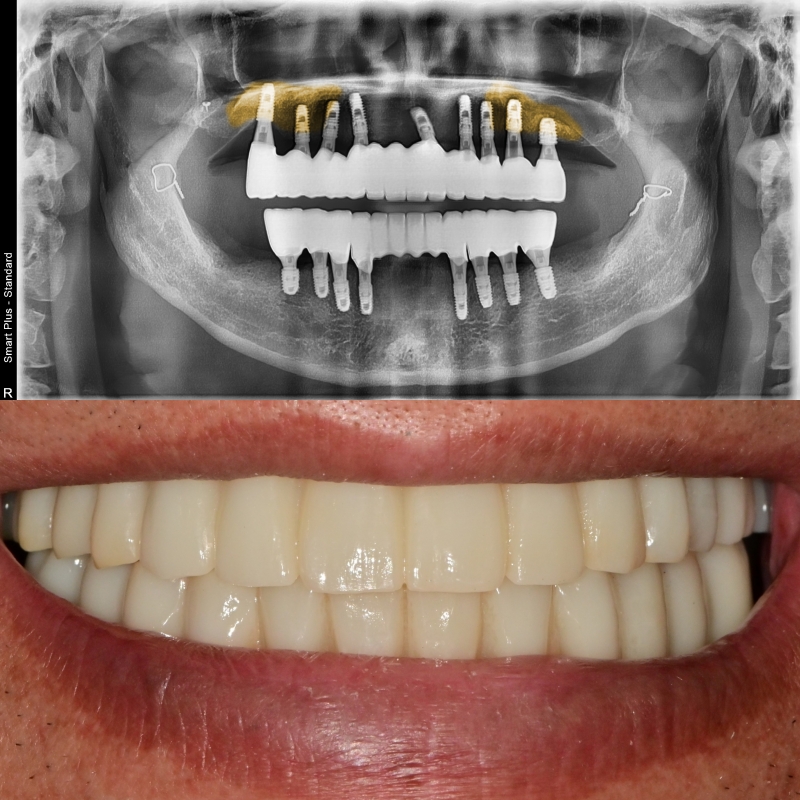

현재 뼈 상태에 맞게 위치와 개수를 정하여 수술을 끝낸 사진입니다.

어금니의 기준점이 없어져 엑스레이의 상이 왜곡되어 나타나 보이지만

의도된 위치에 잘 식립이 되어있음을 확인했습니다.

최종 보철물까지의 완성

원하는 임플란트의 고정값을 얻은 후 최종 보철이 완성되었습니다.

과거에 얇았던 잔존골이 노란색으로 표시된 것처럼 두껍게 뼈가 형성된 것을 볼 수 있습니다.

미소를 지을 때 생기는 스마일 라인도 치료 전보다 훨씬 자연스러운 모습이 되었습니다.

초반에는 턱관절이 안정화가 되지 않아 자주 내원하셔서 체크를 받으셨지만

2년이 지난 최근까지도 임플란트 주위염이라든지 큰 문제점 없이 잘 사용하고 계십니다.